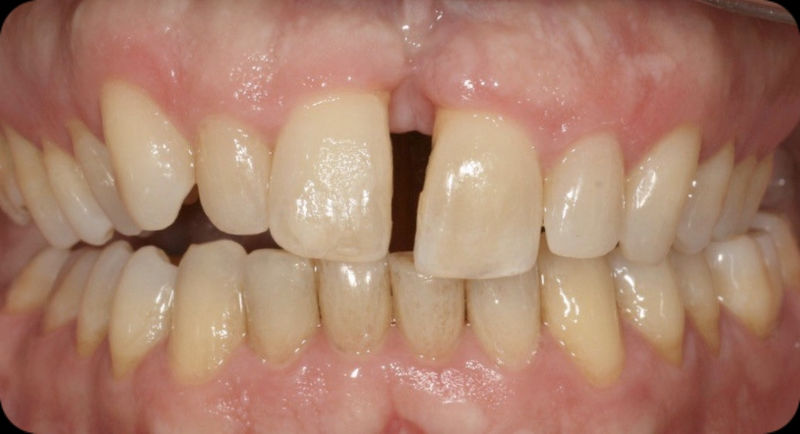

Amplia gama de tratamientos para mejorar la apariencia de la sonrisa, corrigiendo el color, la forma, el tamaño, la alineación y la posición de los dientes. Los procedimientos más comunes y solicitados incluyen el blanqueamiento dental, las carillas y coronas, así como las resinas.

Restauraciones fabricadas en el laboratorio con materiales estéticos, los cuales cubren de manera total dientes anteriores y posteriores. Se utilizan primariamente para restaurar dientes con caries, fracturas y/o defectos amplios, así como soportes de puentes. Para poder enviar el caso al laboratorio se toman impresiones utilizando materiales de impresión o técnicas modernas digitales.

Ortodoncia y coronas.